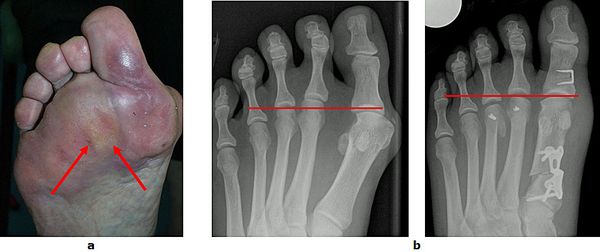

Abb.10: a Schmerzhafte Schwielenbildung unter dem Vorfuß.

b Wiederherstellung der Längenverhältnisse zwischen dem ersten, zweiten und dritten Strahl durch eine Rückverlagerung der Mittelfußköpfchen zwei und drei. Zeitgleich wurde auch der Hallux valgus korrigiert.